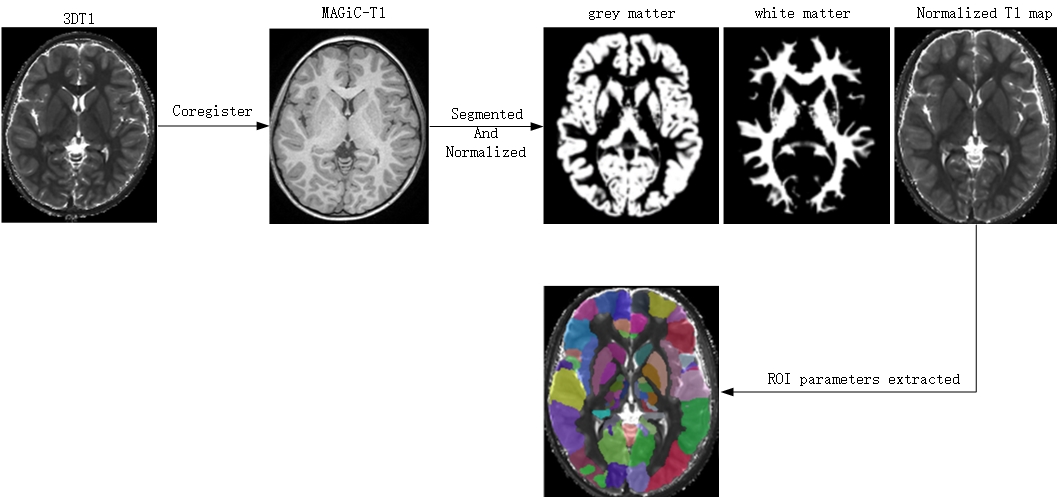

A total of 25 children with ASD and 23 children with DLD at the age of 2-5 years were enrolled. Magnetic resonance data were acquired on a 3.0 T scanner (SIGNA Pioneer, GE Medical Systems, Waukesha, WI, United States). Parameters of Synthetic MRI were as follows: TR = 4230 ms; TE = 20.4 ms; FOV = 24×24 mm2; Slices = 24; scanning time = 4 min 30 s; Parameters of 3D T1-weighted image were as follows: slice thickness = 1 mm; slices = 152; scanning time = 3 min 43 s. T1, T2 mapping and PD images were generated simultaneously on SyMRI 8.0 software (SyntheticMR, Linköping, Sweden). Co-registration and parameters extraction were then performed on SPM software (https://www.fil.ion.ucl.ac.uk/spm/). Cortico-striatal pathway is a common vulnerable brain region in ASD and DLD [5, 6]. The orbitofrontal cortex (OFC) (including medial orbital gyrus, anterior orbital gyrus, posterior orbital gyrus, lateral orbital gyrus), striatum (including the caudate nucleus, putamen, and pallidum), amygdala, and hippocampus are taken as regions of interests (ROIs).

The pipeline of image preprocessing was shown in Figure 1. In group comparisons as shown in Fig. 2, T1 relaxation time of left and right Putamen and the left and right pallidum in the striatum was significantly greater in the DLD group than in the ASD group. For the T2 relaxation time, there were no significant differences between the two groups. In the Receiver operating characteristic (ROC) analyses of the significant indicator in Fig. 3, the largest area under the curve (AUC) is 0.7878 from T1 of right Putamen.

Figure 1 Pipeline of image preprocessing and parameter extraction (with T1 map as an example)